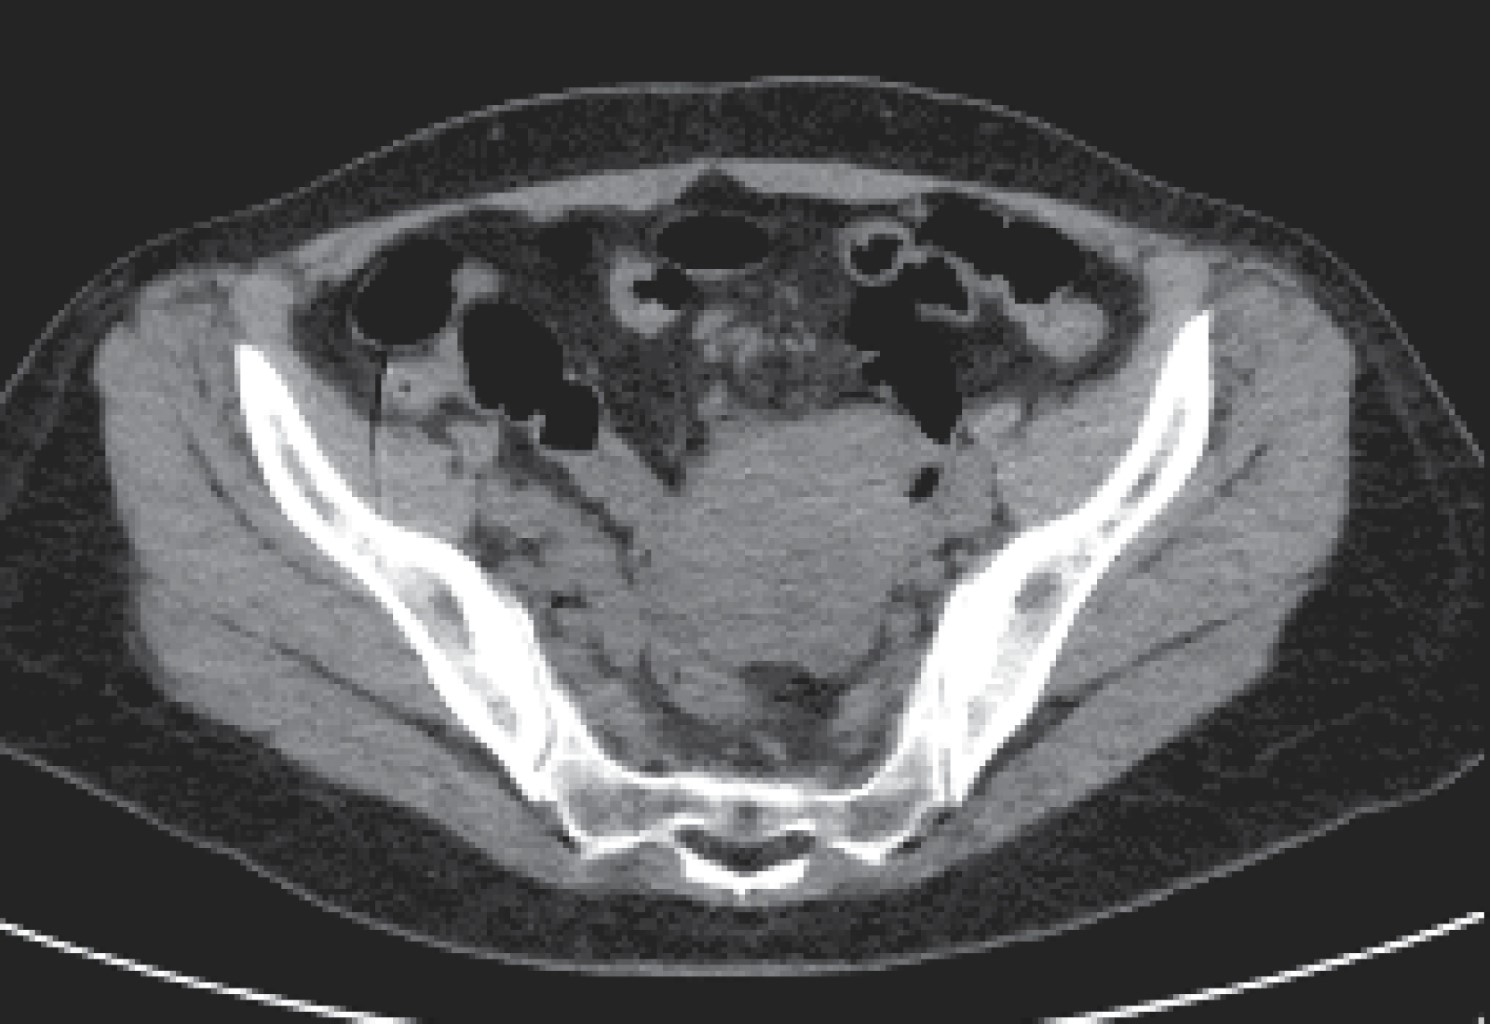

La tomografía axial computada (TAC) revela tumoración estenosante e infiltrante de las paredes del íleon con lumen estrecho y distensión de asas intestinales (Figuras 2 y 3).

Figura 2